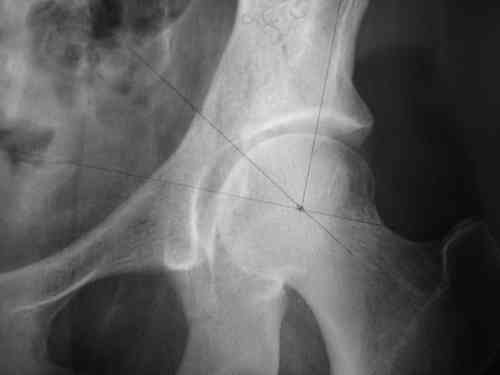

Дорогой Андрей. Мы имеем дело с комбинированной (ротационно и вертикально) нестабильностью таза со смещением правого гнемипелвиса. При таких переломах, фиксация только переднего полукольца вне зависимости от метода фиксации, как уже было сказано Djoldas Kuldjanov, M.D., не может создать адекватной фиксации. И перелом пластины был вполне ожидаемым после активизации пациента. Смещение сохраняется, и по-видимому не 2 см., а все 4, если не более. Разница всего (+2 см) по конечностям как вы указываете, скорее скомпенсировано позвоночником и протезом. Дополнительные снимки или КТ исследование помогли бы уточнить степень смещения с точностью до мм., выявить перелом поперечного отростка пятого поясничного позвонка, или помимо разрыва правого крестцово-подвздошного сочленения выявить перелом боковой массы крестца справа и т.д. При возможности, конечно, все это желательно сделать. Но мало что изменится с практической точки зрения, т.к. задача - это низведение репозиция и надежная фиксация правого гемипелвиса. Учитывая плачевный опыт стержневого аппарата, давность травмы совершенно очевидно, что поставленная задача достижима при открытой репозиции и одномоментной фиксации переднего полукольца с артродезированием правого крестцово-подвздошного сустава. Операция выполняется в положении больного на здоровом боку или полубоку из расширенного трансоссального подвздошно-пахового доступа с переходом на лонное сочленение доступом по Pfannenstiel. Указанный доступ обеспечивает подход к крестцово-подвздошному сочленению как спереди так и сзади. После артродезирования выполняется синтез лонного сочленения. Клинический пример

Пациентка С.26 лет. Травма за 6 месяцев до поступления

Укорочение правой нижней конечности до 10см